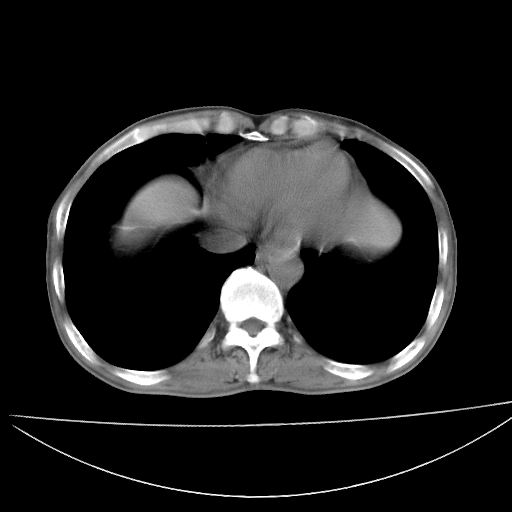

以下是引用杀毒软件在2009-4-28 17:58:00的发言:[br]考虑----左肺慢性肺脓肿形成继发上叶含气不良---抗炎后复查---待排肿瘤所致[br][br][本贴已被 杀毒软件 于 2009-4-28 18:01:26 修改过]